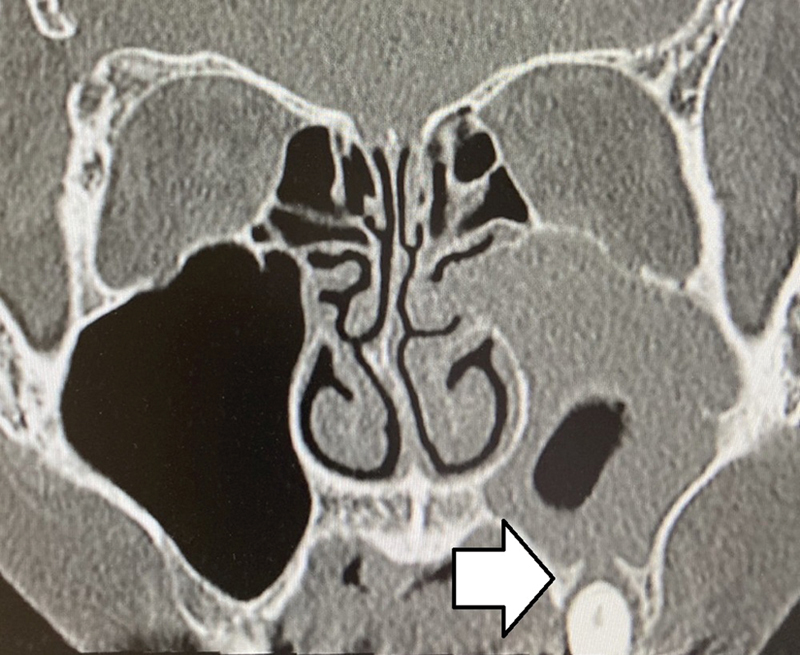

Introduction  There are no clear guidelines for deciding between endoscopic sinus surgery and tooth extraction for the treatment of odontogenic sinusitis. Furthermore, tooth extraction does not necessarily improve sinusitis and eventually results in additional endoscopic sinus surgery. Objective  The present study aimed to retrospectively investigate negative predictive factors of tooth extraction for odontogenic sinusitis. Methods  In total, 22 patients with odontogenic sinusitis, who underwent tooth extraction between April 2017 and March 2021, were included. The patients were divided into the improved (n = 15) and non-improved (n = 7) groups. Subsequently, the two groups were compared. Results  A higher percentage of patients in the non-improved group had polyps in the middle nasal meatus ( p  = 0.0008), higher Lund-Mackay score (LMS) ( p  = 0.0008), and apical lesions penetrating the maxillary sinus ( p  = 0.113). Patients with middle nasal meatus polyps, with LMS ≥ 7, or with a combination of apical lesions penetrating the maxillary sinus and LMS ≥ 5, were less likely to see improvement in sinusitis with tooth extraction. Conclusion  Tooth extraction as the initial intervention for odontogenic sinusitis presents a higher risk of failure, particularly in cases in which polyps are present in the middle nasal meatus, with LMS ≥ 7, or with a combination of apical lesions penetrating the maxillary sinus and LMS ≥ 5.